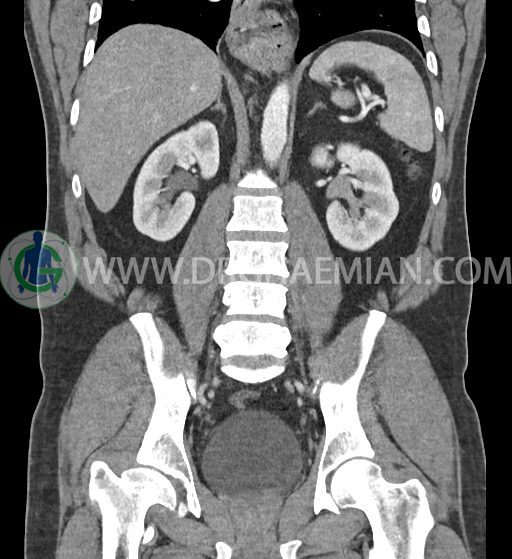

در سی تی اسکن اسپیرال شکم و لگن با کنتراست خوراکی و وریدی (مولتی دیدکتور 16 با مقاطع ظریف و بازسازی های ساژیتال و کرونال) :

کلیه ها کنتراست را ترشح کرده اند و نمای سیستم پیلوکالیسیل و حالب دو طرف نرمال است .

-هیدرویورترونفروز جزئی دو طرفه دیده می شود که می تواند ثانویه به اتساع مثانه باشد.